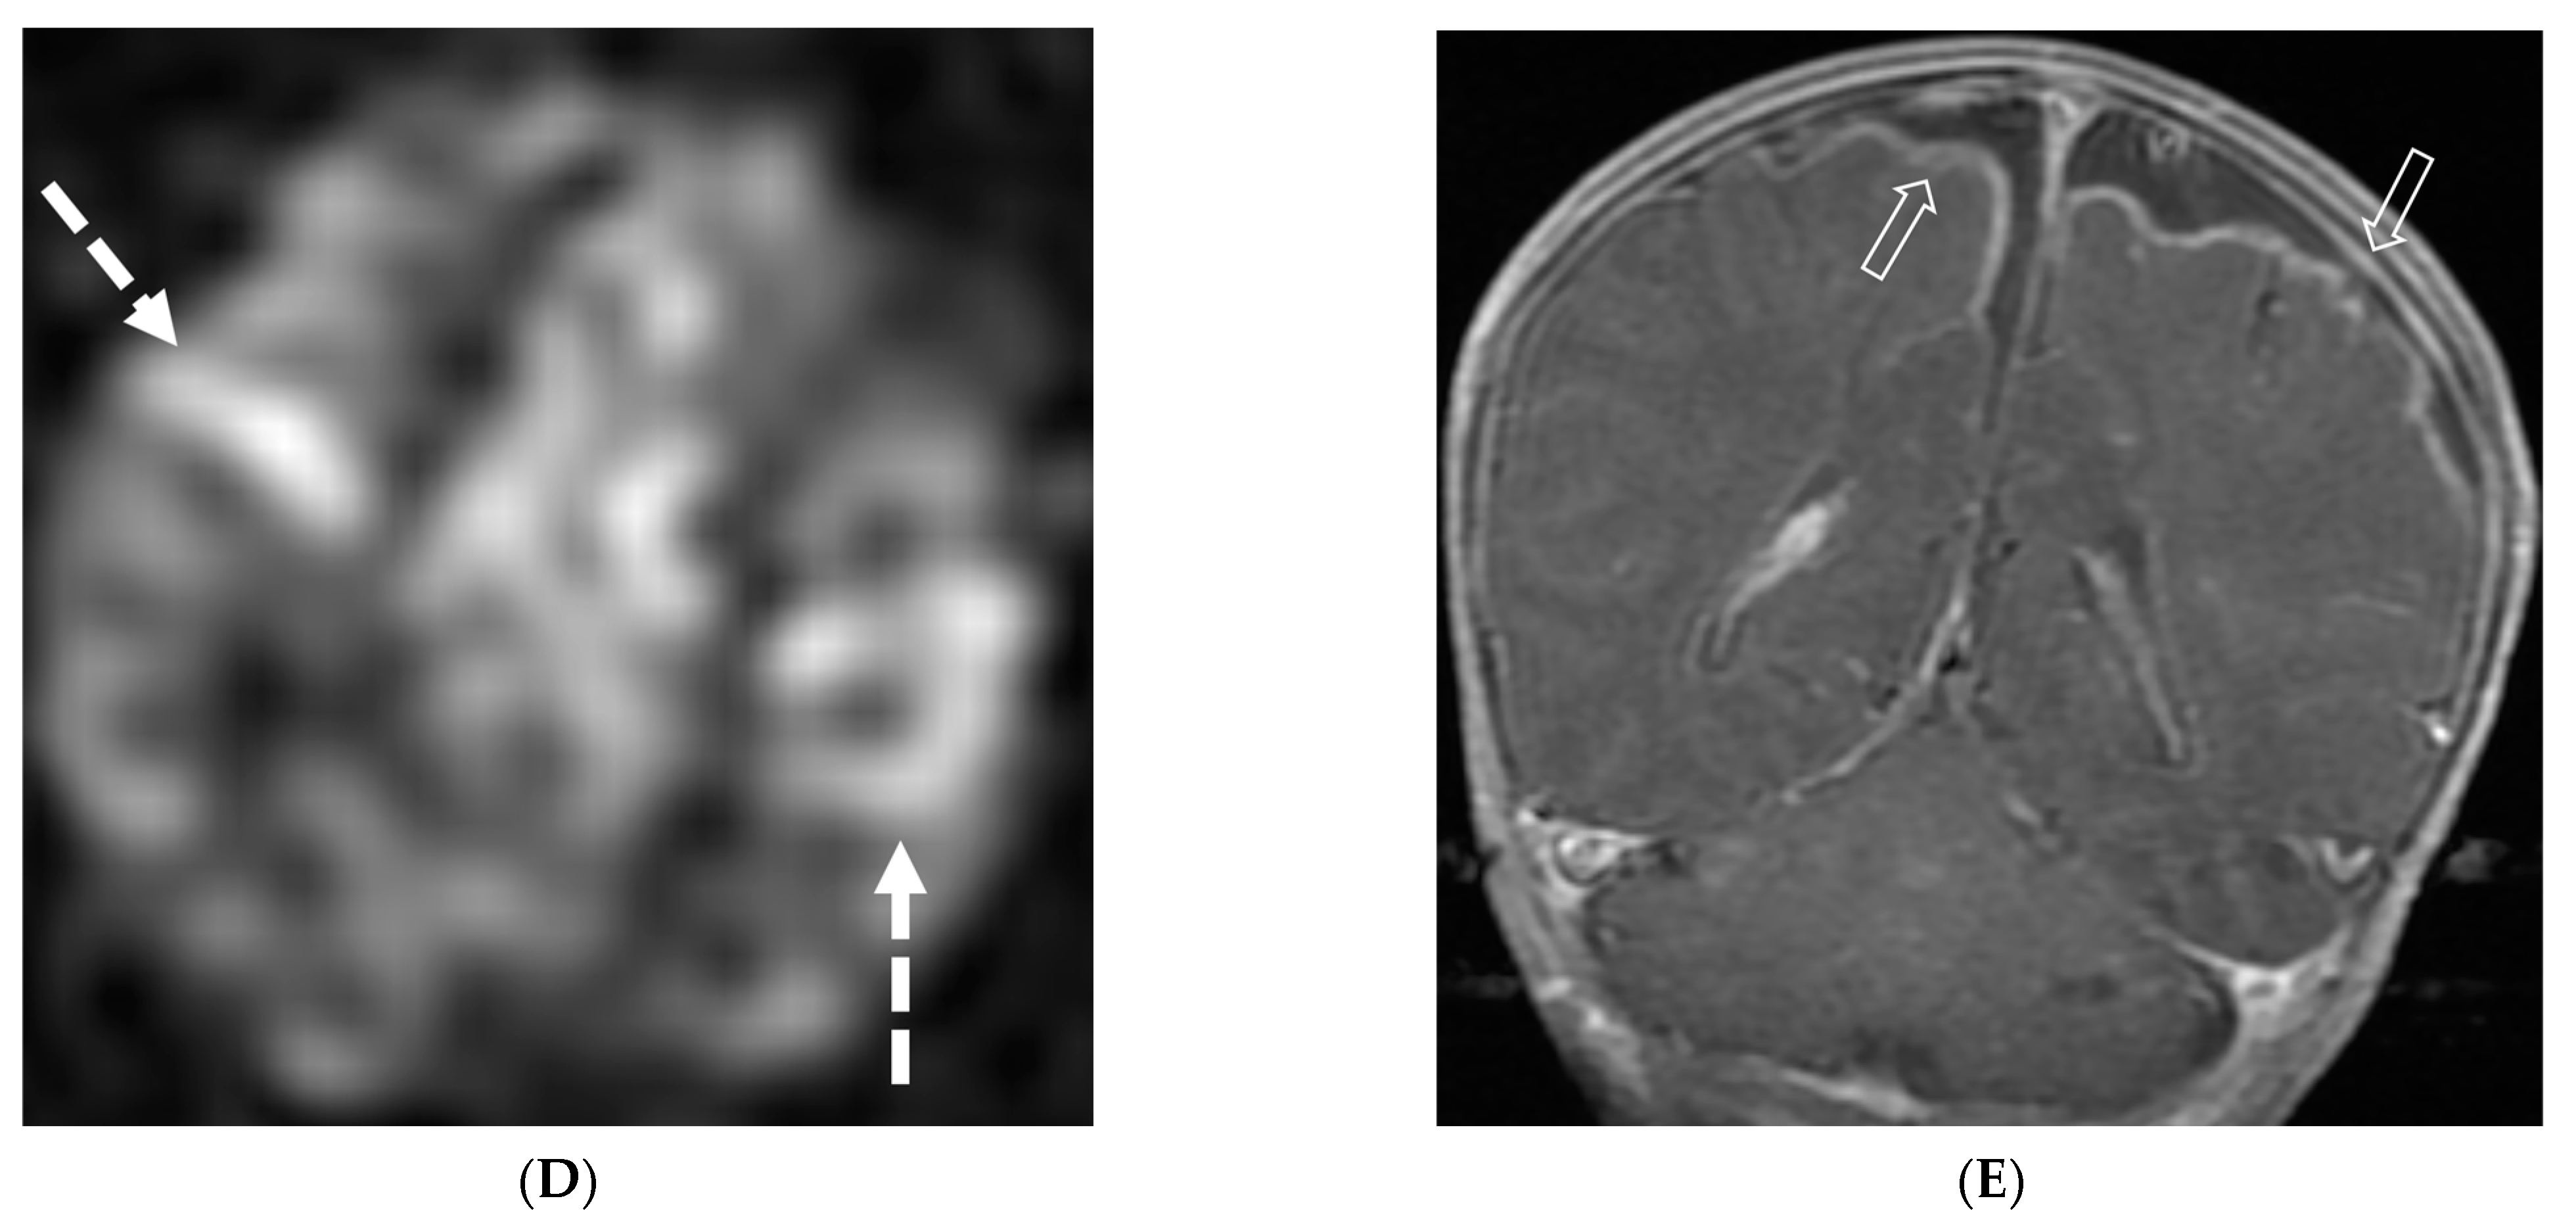

TBM is characterized by LME, predominantly smooth and localized in the basal cisterns [76]. In severe cases, this can lead to the formation of basal exudates, visible as enhancing fluid in the basal cisterns [77]. The disease is often accompanied by parenchymal abnormalities, most commonly conglomerated ring-enhancing lesions with characteristic T2 hypointensity due to caseous content, although liquefaction may cause the core to become T2 hyperintense [78]. These ring-enhancing lesions can potentially coalesce to form abscesses. TBM may also present with infarcts in the thalami or basal ganglia due to basal vasculitis (Figure 13) [78]. The meningeal involvement typically occurs through hematogenous spread, and the condition is most prevalent in children and young adults presenting with altered mental status [79]. These imaging findings along with lymphocyte predominant CSF and significantly high protein can be diagnosed as tuberculosis since culture can take weeks.

Figure 13.

Axial T1 FS (A,B) and sagittal T1 fat sat (C,D). 2-year-old girl presented with emesis, fever and status epilepticus. Septic work up revealed tubercular meningitis. Extensive abnormal enhancement is seen in the meninges, prominent in the basilar cisterns (arrows). Ring-enhancing tuberculomas are seen in the cerebellum adjacent to the fourth ventricle and in the brainstem (curved arrows). Diffuse meningeal enhancement and thickening throughout the spinal canal as well as enhancement of the nerve roots is seen (dashed arrows).